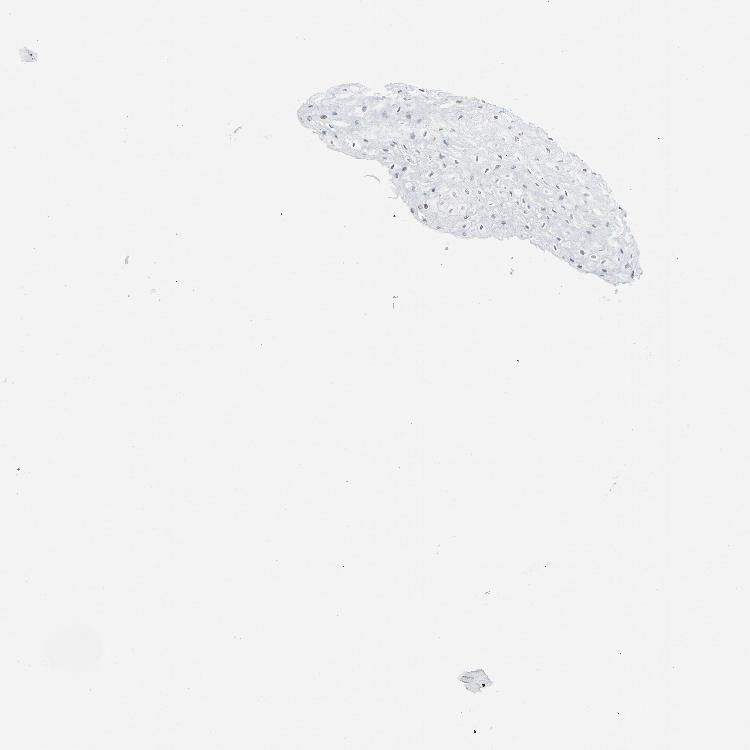

ESOPHAGUS - Antibody stainingi

Antibody staining in the annotated cell types in the current human tissue is reported as not detected, low, medium, or high, based on conventional immunohistochemistry profiling in selected tissues. This score is based on the combination of the staining intensity and fraction of stained cells.

Each image is clickable and will lead to virtual microscopy that enables deeper exploration of all samples and also displays staining intensity scores, fraction scores and subcellular localization as well as patient and tissue information for each sample.

Antibody HPA008888Antibody CAB004239

Squamous epithelial cells HighHigh